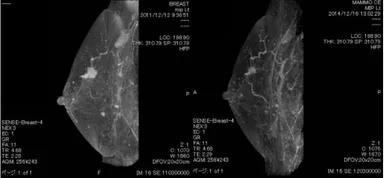

・早期の乳がんの方が、本人の希望により『RNA干渉療法』を選択。2008年位治療をスタートし、ガン細胞が縮小。今にも消失しそうな状況となっている。